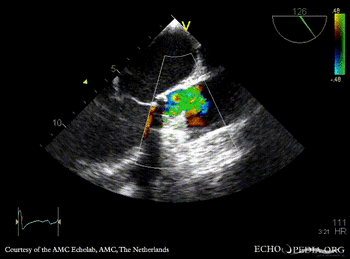

Thrombus of prosthetic aortic valve

TEE: thrombus of prosthetic aortic valve TEE: severe aortic regirgitation